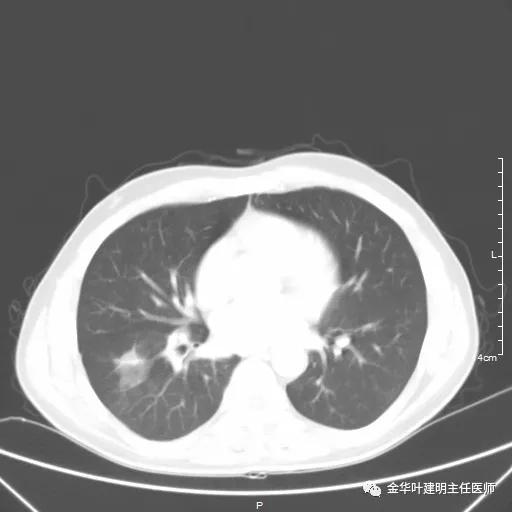

如果选取肿瘤所在的层面来看,则是以下图像:

以上是肺窗,见右肺下叶实性占位,有毛刺、浅分叶、膨胀性,血管征等,是较为典型的恶性肿瘤。